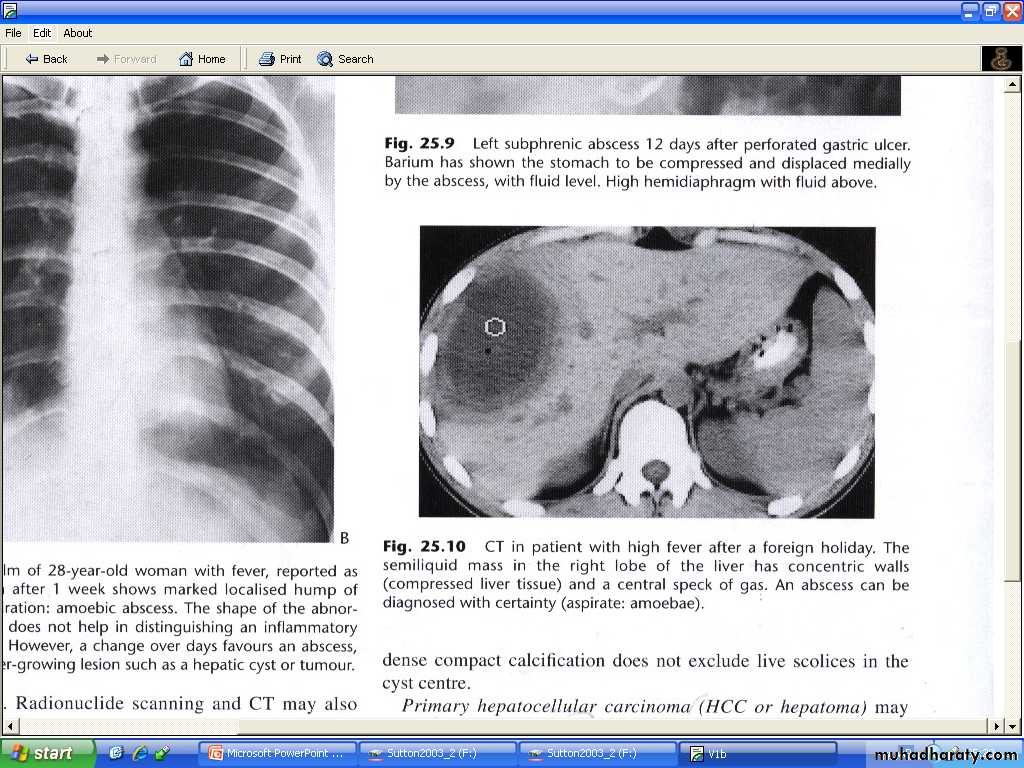

Both of these conditions appear as enhancing masses on CT.Liver abscess :

Hepatic abscess tend to have fluid centers , with walls that are thicker , more irregular and more obvious than those of simple cysts.At CT : the core fluid have attenuation values may be same as water , usually they are higher .

At US : necrotic debris may be seen within the abscess.

Occasionally chronic abscess calcify.

Abscess cannot usually be differentiated from necrotic tumor by US,CT or MRI, clinical situation should be aid in distinction.